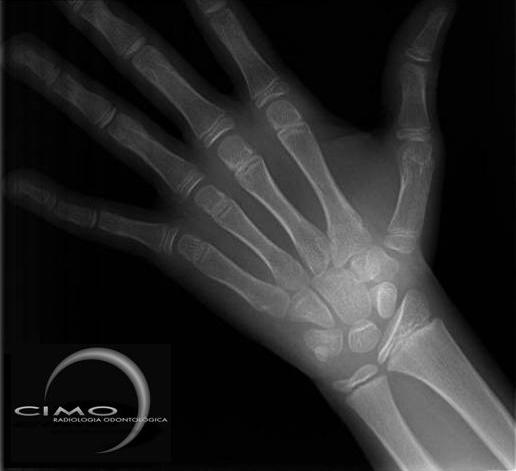

CARPAL

Devido à grande quantidade de centros de ossificação contidos na mão e punho a radiografia carpal é usada como diagnóstico da maturidade óssea. Através dos dados obtidos pelo Dr. Tavano (USP Bauru) em crianças brasileiras, este recurso fornece ao profissional a curva de crescimento individualizado do paciente, indicando em que etapa do surto este se encontra, bem como quanto tempo falta para o final desse crescimento.